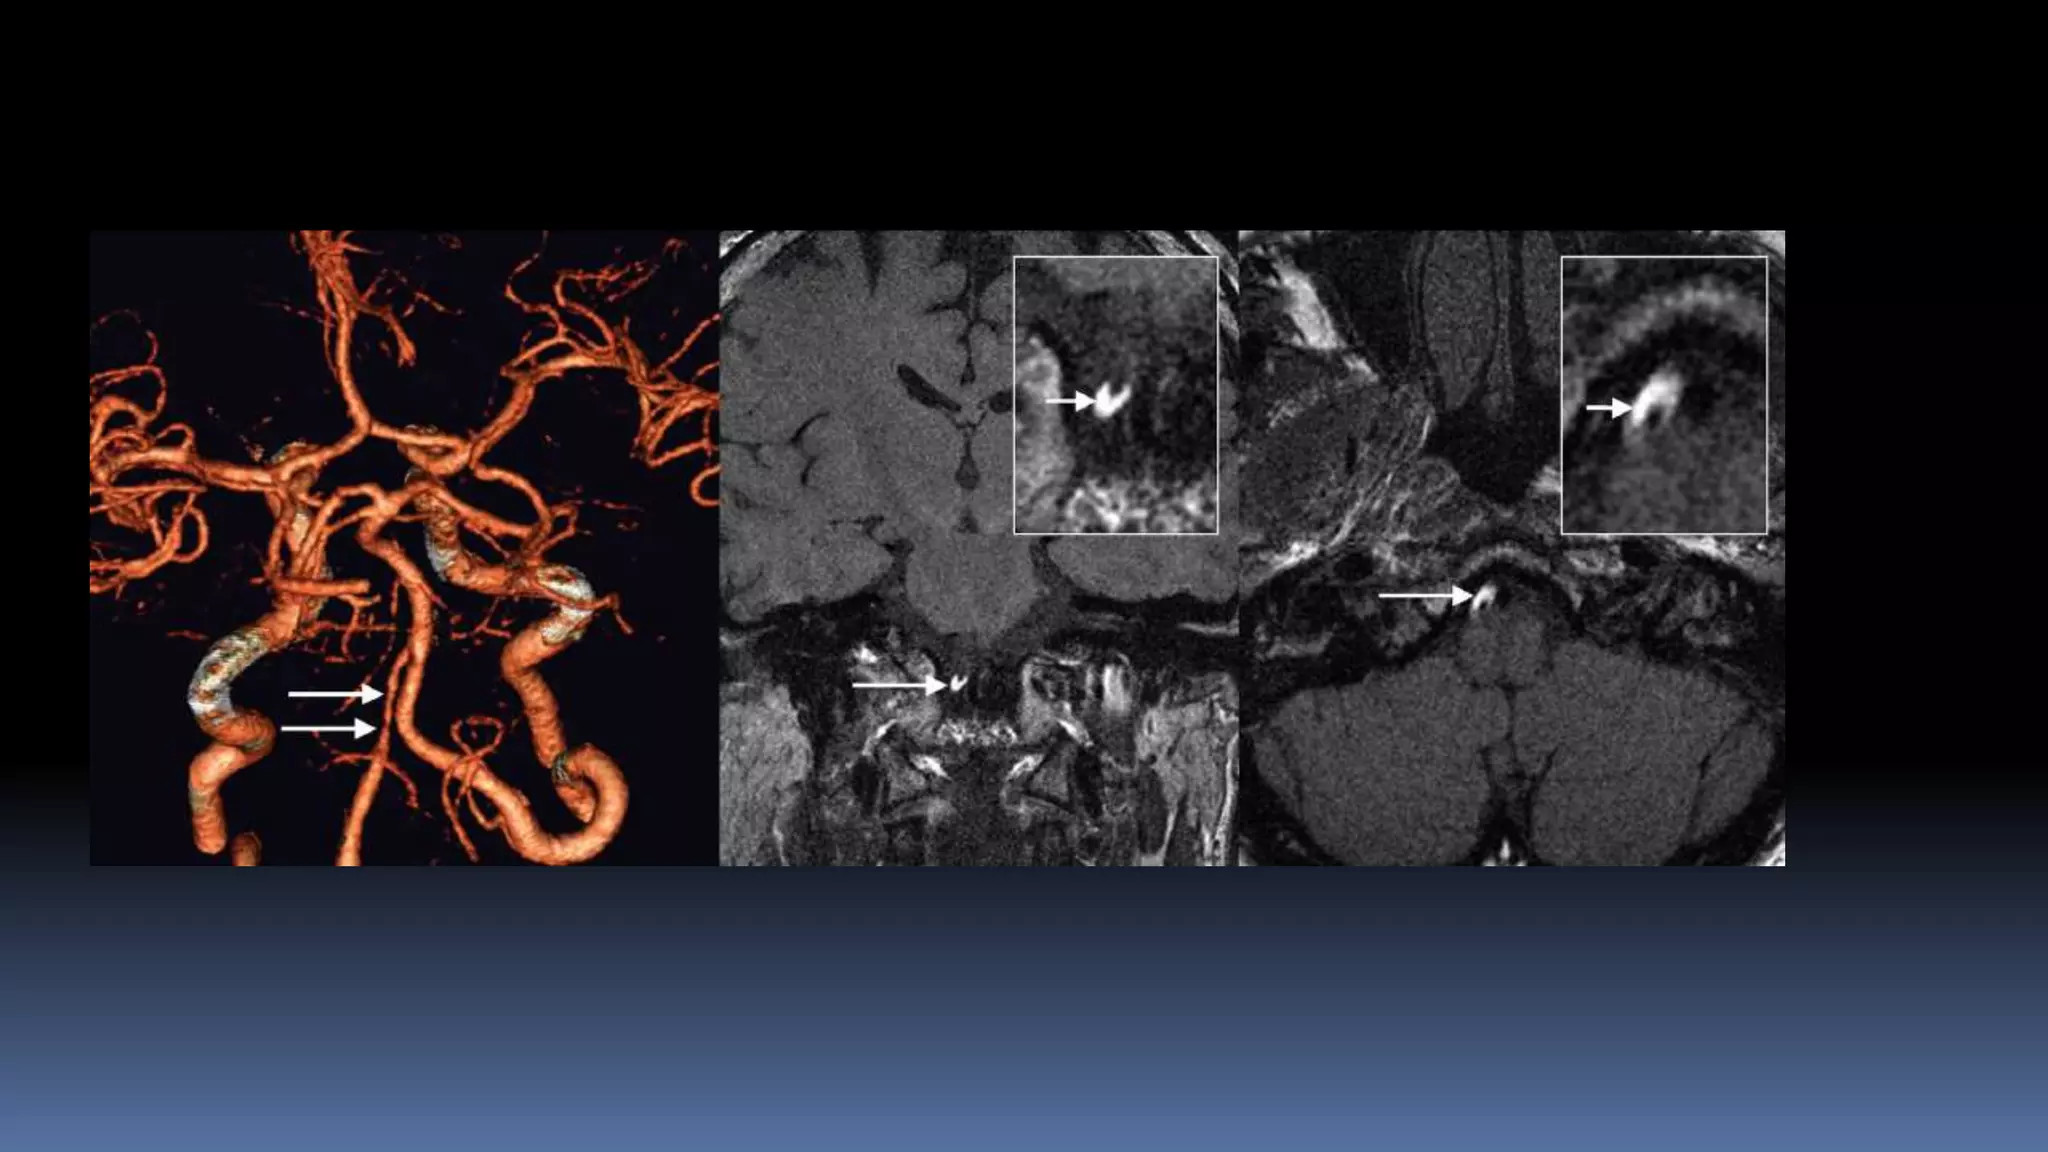

Vessel wall imaging

•MR vessel wall imaging is a powerful tool for extracranial (eg, carotid)

plaque characterization, enabling the determination of stroke risk from

carotid plaque rupture

•The Multi-Ethnic Study of Atherosclerosis carotid MR imaging study first

reported associations of carotid plaque features with future events. It

showed that the remodeling index and lipid core presence measured

on MR imaging added a risk for a new event beyond traditional risk

factors in individuals without a history of cardiovascular disease.

Vessel wall imaging •MRvessel wall imaging is a powerful tool for extracranial (eg, carotid) plaque characterization, enabling the determination of stroke risk from carotid plaque rupture •The Multi-Ethnic Study of Atherosclerosis carotid MR imaging study first reported associations of carotid plaque features with future events. It showed that the remodeling index and lipid core presence measured on MR imaging added a risk for a new event beyond traditional risk factors in individuals without a history of cardiovascular disease.